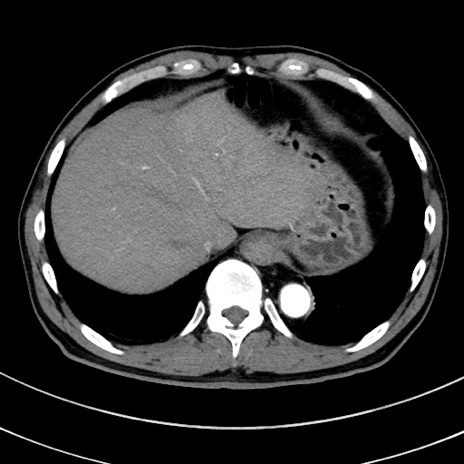

症例8(横断像)

【症例】 60歳代男性

【主訴】 黒色吐物

【現病歴】 4日前から嘔気自覚、2日前の朝食後にも嘔気あり、自分で手で嘔吐反射起こし嘔吐したところ血が混ざっていたため受診。

【既往歴】 5年前汎発性腹膜炎を伴う急性虫垂炎で手術、高血圧、前立腺肥大症、高脂血症

【身体所見】 腹部正中に手術癩痕あり 腹部平坦・軟圧痛なし膨満感あり

【データ】WBC 8400、CRP 4.54